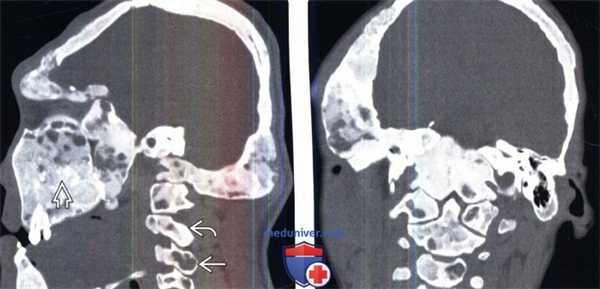

(Слева) Сагиттальный КТ-срез: тяжелый случай полиостозной формы фиброзной дисплазии (ФД) с поражением черепа, лицевого скелета и шейного отдела позвоночника. Некоторые очаги поражения имеют вид «матового стекла», тогда как другие-чисто литические. Также визуализируются отдельные фокусы кальцифицированного хряща.

(Справа) На фронтальном КТ-срезе у этого же пациента не прослеживается трабекулярная структура большинства видимых на срезе костей вследствие замещения трабекул фиброзным матриксом. Истончение компактных пластинок плоских костей черепа является характерным признаком заболевания.